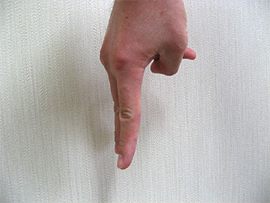

平面写真と現実の立体物体の差

ここで「平面写真」と「現実の立体物体」の差について、写真を交えて説明します。

下の写真をご覧下さい。

正面から撮影した手ですが、指が2本見えています。

そして次の写真をご覧下さい。違う方向から撮影したら指は3本うつっています。

さらに一本目と二本目との間隔は開いていますが、二本目と三本目との間隔はほとんどないことがわかります。このようなことが現実に歯科の治療現場で起きているのです。

このように平面画像で見た場合だけでは、実際の物体がどうなっているのかを正確に捕らえることができないということが言えます。